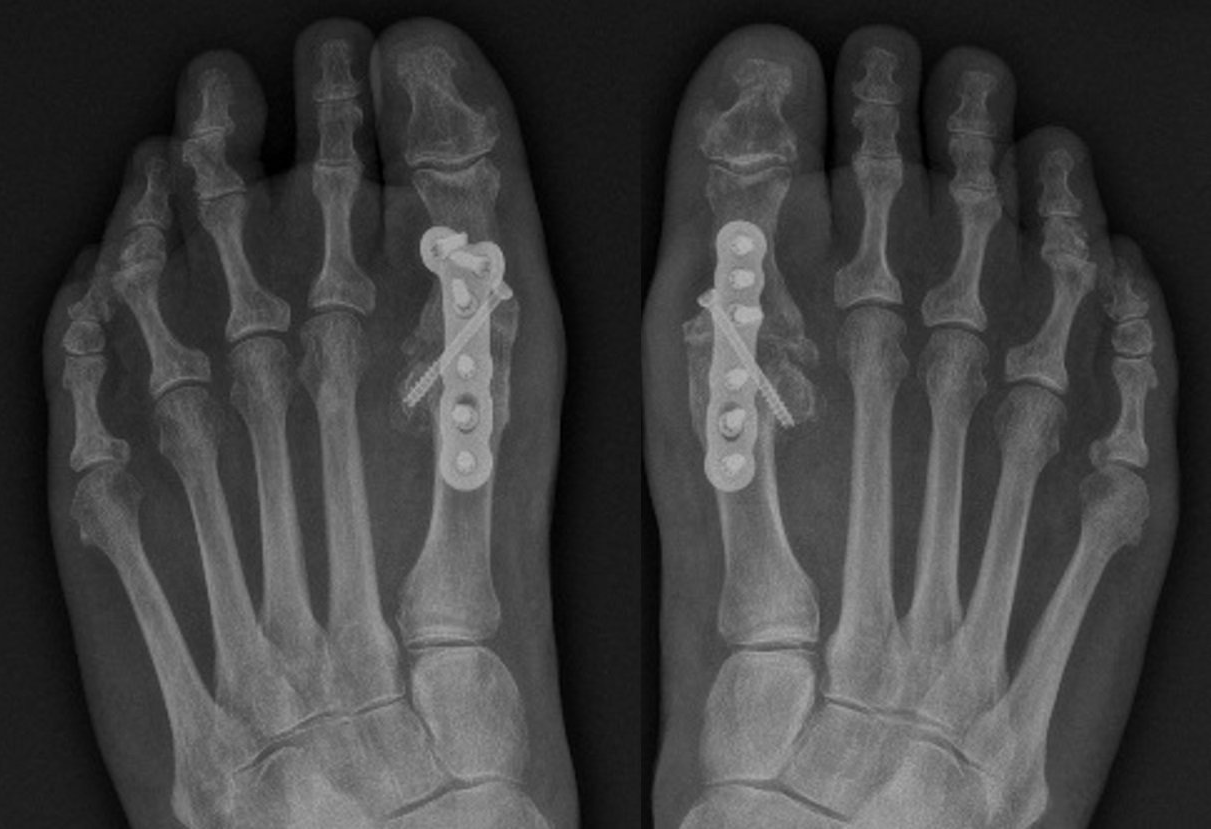

This surgical procedure involves fusing the 1st MTP joint in a functional position.

- The worn joint surfaces (cartilage) are removed to healthy bone and joined together with a metal plate and screws.

- Over several months these bones grow together into a single bone.